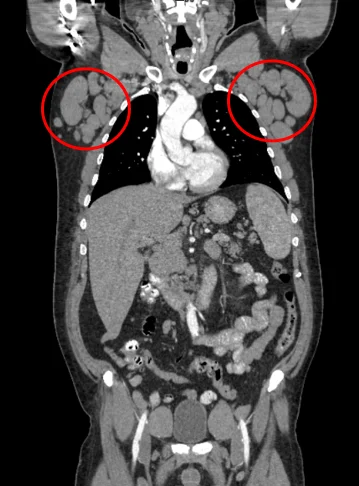

___Вот такими большими были лимфатические узлы у пациента перед началом лечения: